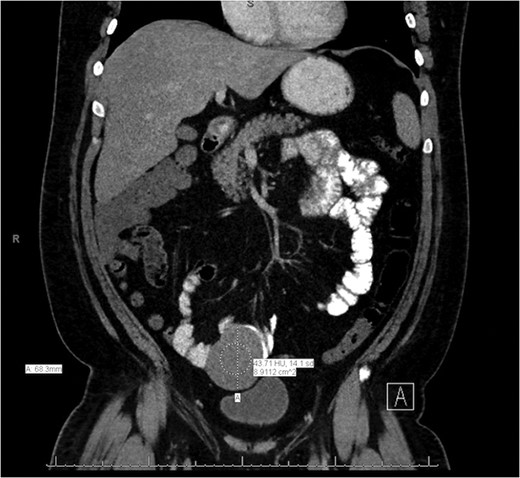

A CT of the abdomen and pelvis without contrast was obtained on admission and revealed a 7 × 7.6 cm2 mass with CT attenuation of 37.34 Hounsfield units within the anterior left midpelvis. It appeared to be inseparable along its superior aspect from a loop of bowel, and it was felt to possibly be an unusual diverticulum. The patient was given intravenous fluids and one unit of packed red blood cells for his symptomatic anemia with continued rectal bleeding. He was also empirically started on Cipro and Flagyl for possible infection coverage. GI was consulted and the patient was taken for an EGD and colonoscopy; however, both were negative for any acute pathology.

General surgery was then consulted for further recommendations. A CT of the abdomen and pelvis with contrast was performed and demonstrated a 7.2 × 6.8 × 6.1 cm3 lesion arising from the mid-to-distal small bowel loop with no evidence of significant enhancement. It appeared mobile within the mesentery of the small bowel when compared to previous imaging (Figs. 1 and 2). The patient had continued to bleed and required transfusion with five units of packed red blood cells; therefore, it was decided to take the patient to the operating room for a diagnostic laparoscopy.

Axial slice of the CT of the abdomen/pelvis demonstrating a lesion arising from the mid-to-distal small bowel.